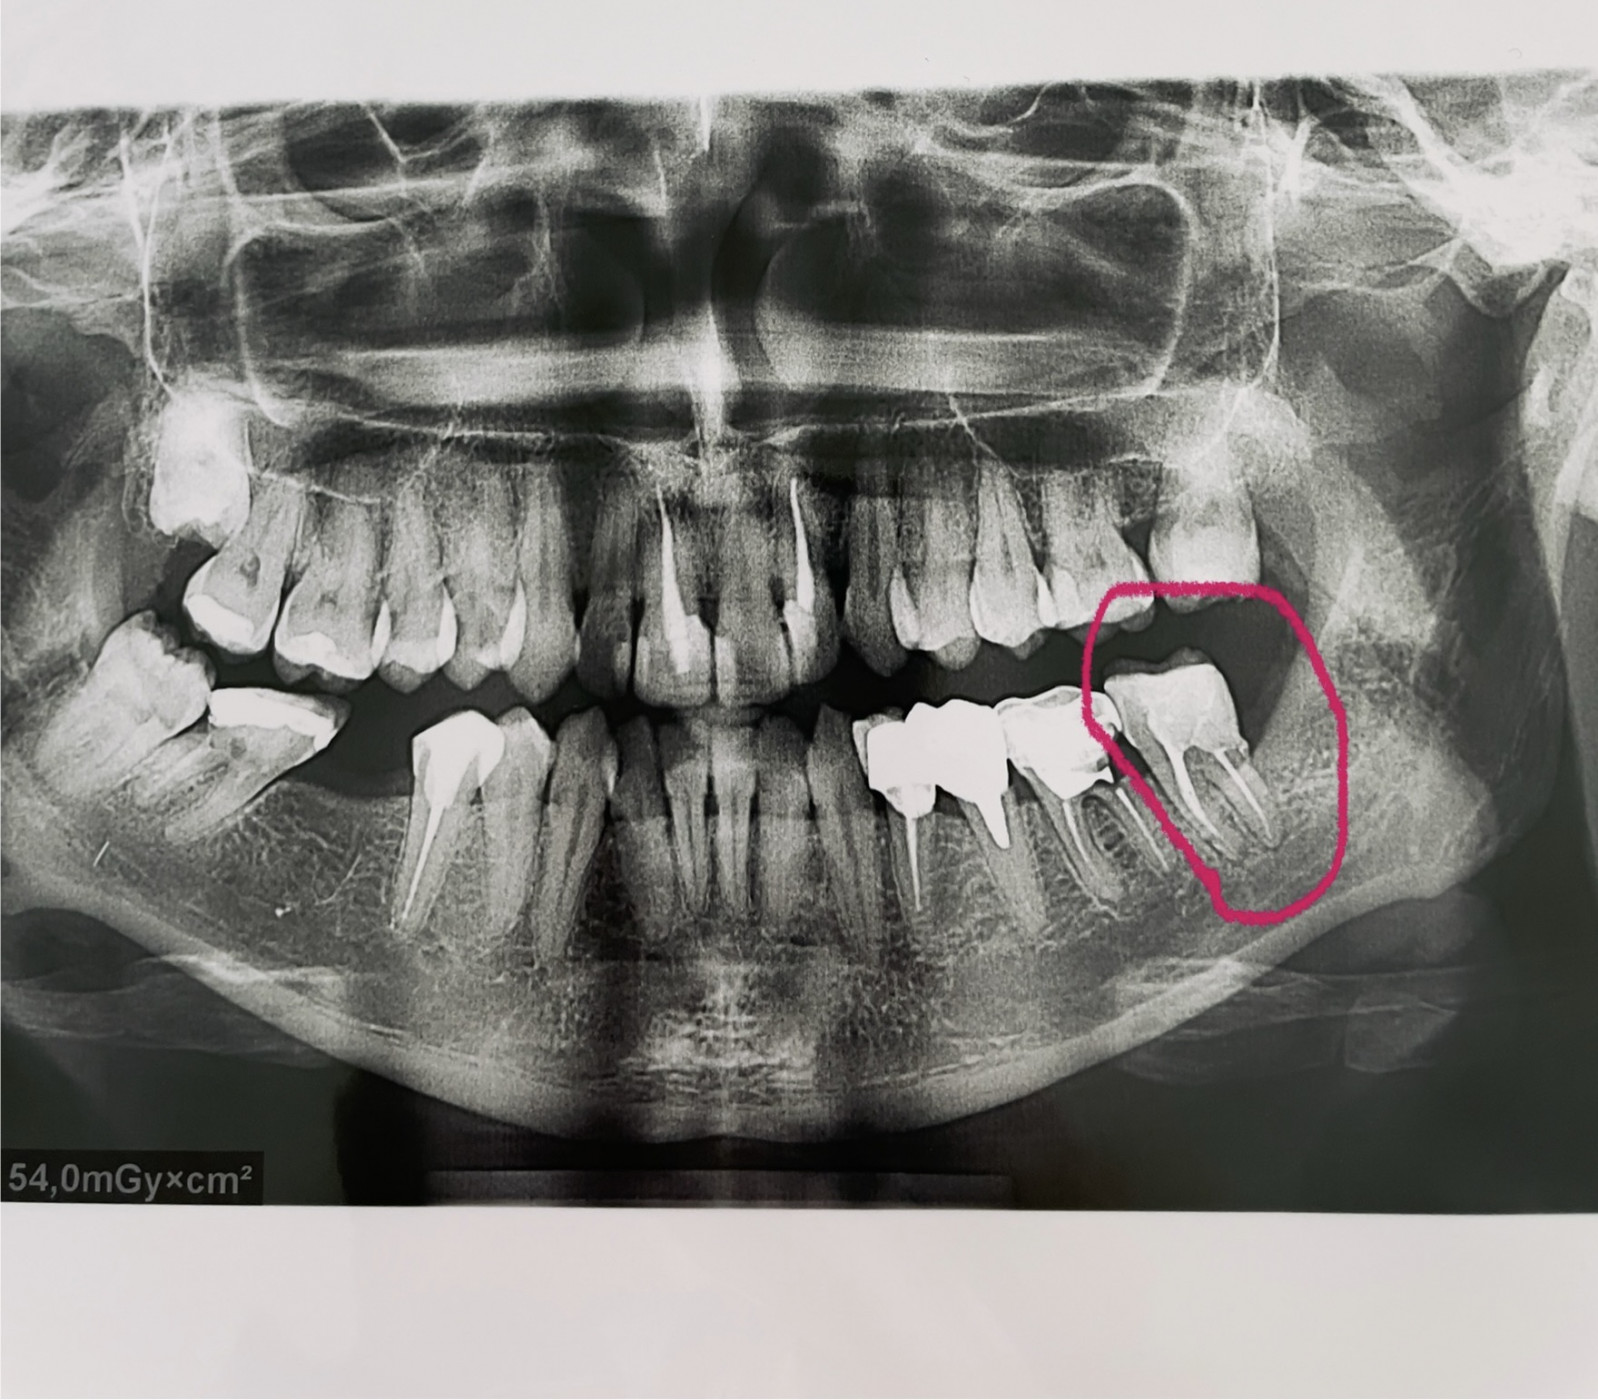

Удалять или лечить?